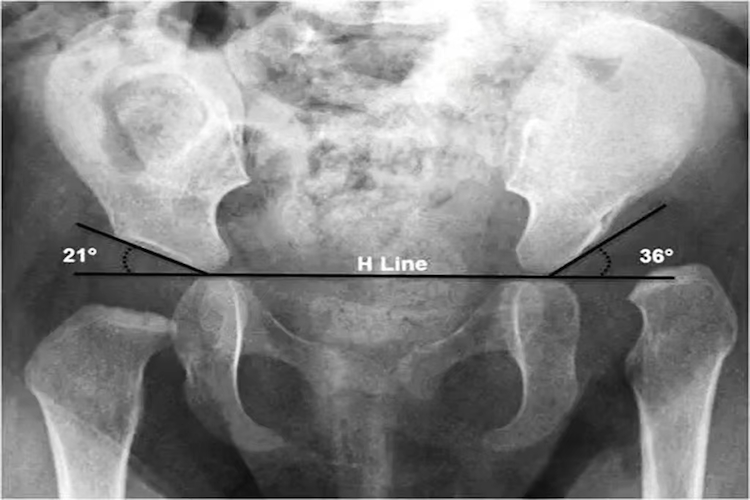

影像检查:如超声、X光检查等。超声灵敏度较高,可早期检查到髋臼发育异常,X线检查可发现髋臼发育不良、半脱位或脱位。一般在骨盆正位X线平片上画定几条连线有助于诊断。